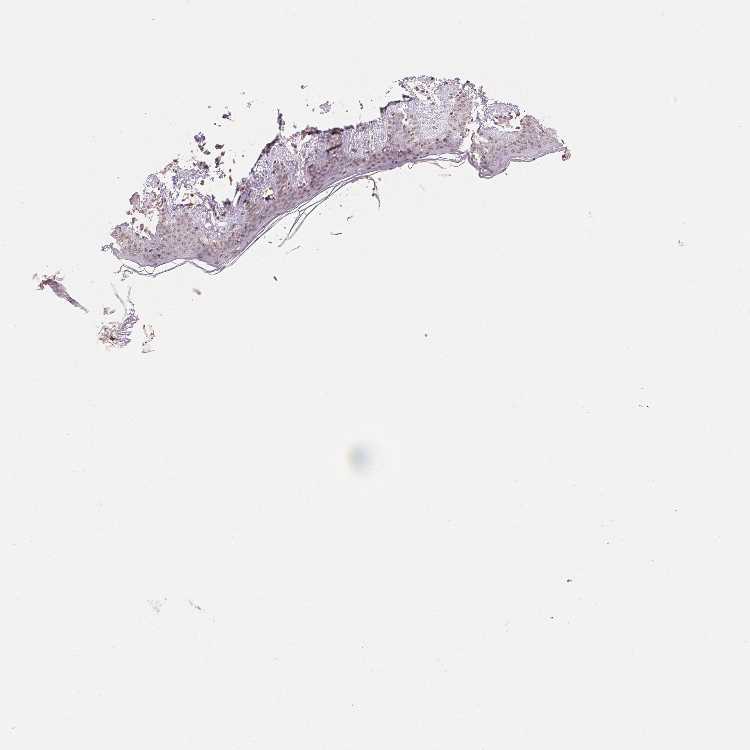

SKIN 1 - Antibody stainingi

Antibody staining in the annotated cell types in the current human tissue is reported as not detected, low, medium, or high, based on conventional immunohistochemistry profiling in selected tissues. This score is based on the combination of the staining intensity and fraction of stained cells.

Each image is clickable and will lead to virtual microscopy that enables deeper exploration of all samples and also displays staining intensity scores, fraction scores and subcellular localization as well as patient and tissue information for each sample.

Antibody HPA049805

Langerhans Low

Fibroblasts Low

Keratinocytes Low

Melanocytes Low